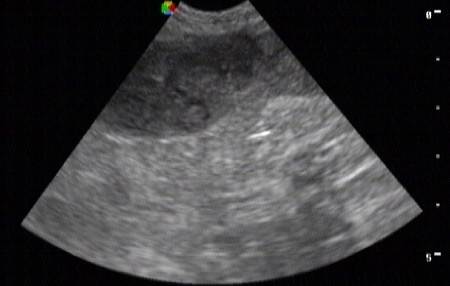

腹部B超报告

腹部B超报告,

胆囊B超